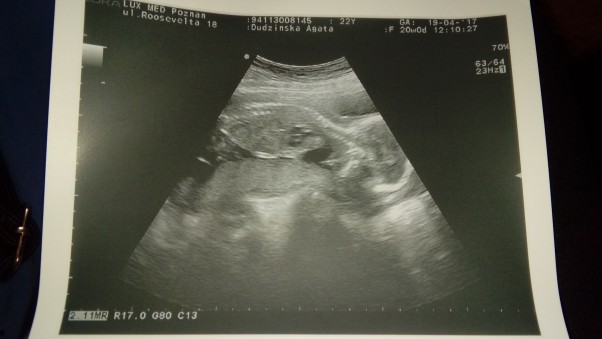

Polówkowe

My juz po polowkowych wszystko jak najbardziej wporzadeczku lekarz nie mial sie do czego doczepic tak bardzo sie ciesze. Teraz rosnij coreczko i za okolo 17 tygodni sie wkoncu zobaczymy.